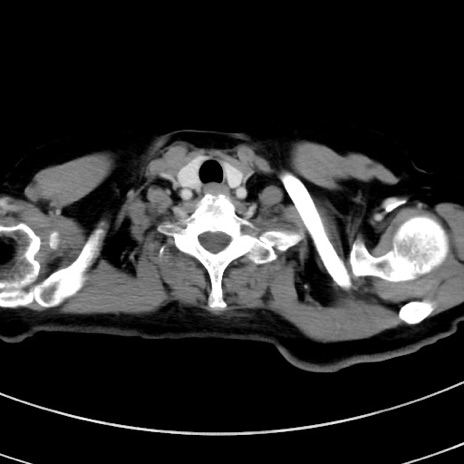

症例9(横断像)

【症例】 60歳代女性

【主訴】むかつき、みぞおちの痛み

【現病歴】3日前よりむかつきがあり、食事がとれない。

【既往歴】糖尿病

【身体所見】発熱なし、心窩部圧痛軽度あるも、腹膜刺激症状なし。

【データ】WBC 7400、CRP 1.92